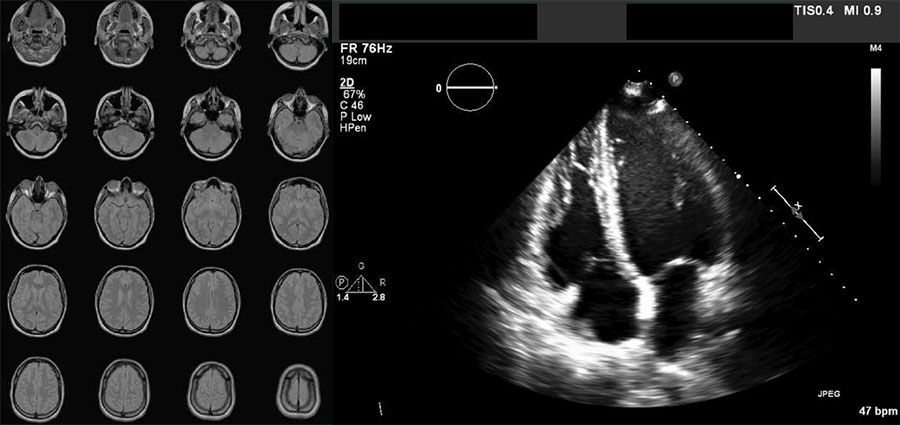

DICOM 형식 영상의 예: 뇌 MRI 스캔을 통해 얻은 일련의 20개 영상 및 심장 초음파 영상.

DICOM 형식으로 저장된 일련의 뇌 MR 영상(왼쪽) 및 심장 초음파 스캔(오른쪽).